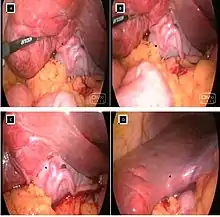

{{cite book}}: CS1 maint: location missing publisher (link) - 1 2 3 4 Balija, M; Huis, M; Nikolic, V; Stulhofer, M (1999). "Laparoscopic visualization of the cystic artery anatomy". World Journal of Surgery. 23 (7): 703–7, discussion 707. doi:10.1007/pl00012372. PMID 10390590. S2CID 23174989.